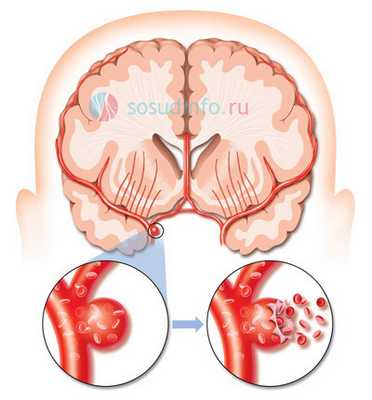

Аневризма сосудов головного мозга - это серьезное заболевание, при котором в стенке артерий головного мозга образуется локальное выпячивание, обусловленное истончением и потерей эластичности пораженного участка стенки. Как показывает статистика, с данной патологией сталкивается около 5% населения. При отсутствии лечения она может осложняться таким жизнеугрожающим состоянием, как разрыв аневризмы. Основным методом лечения этой болезни является хирургическое вмешательство. В данное статье мы поговорим о такой оперативной технике, как клипирование аневризмы сосудов головного мозга.

Клипирование аневризм сосудов головного мозга является довольно сложной операцией, требующей проведения трепанации черепа. Суть данного метода заключается в наложении специального устройства, называемого клипсой, на шейку аневризмы с внешней стороны сосуда. Таким образом патологически измененный участок отсекается от общего кровотока.

Из клинических проявлений аневризмы головного мозга можно отметить как незначительные признаки (головные боли, тошнота, общая слабость, нечеткость и помутнение зрения), так и яркую симптоматику, обусловленную не только значительными размерами аневризмы, но и спонтанным ее разрывом с возникновением кровоизлияния в мозг. Опасность аневризмы в том, что человек с ее разрывом и кровоизлиянием может просто мгновенно погибнуть или остаться глубоким инвалидом. Поэтому при диагностированной аневризме сосудов головного мозга принимается решение о ее клипировании или эмболизации.

Клипирование аневризмы головного мозга - это наложение специального устройства, называемого клипсой, на шейку аневризмы с внешней стороны сосуда. Такая операция является одной из самых сложных в нейрохирургии и проводится с помощью открытого доступа - трепанации черепа.